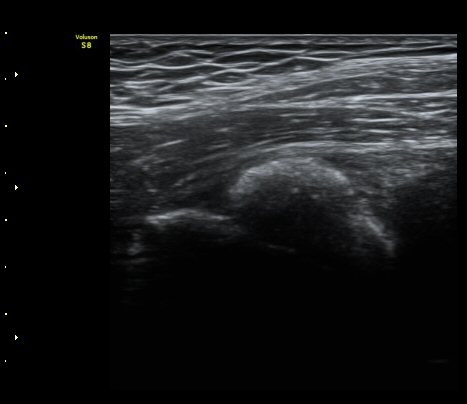

ÃÊÀ½ÆÄ °Ë»ç

¾ûµ¢ÀÌ °üÀý Á¾´Ü¸é°Ë»ç¿¡¼­ ƯÀÌ ¼Ò°ßÀ» º¸ÀÌÁö ¾ÊÀ½(»çÁø 1).

ŽÃËÀÚ¸¦ ¾ûµ¢ÀÌ °üÀý ¿ÜÃø Á¾´Ü¸é°Ë»ç ½Ã ÀüÇÏÀ屨(AIIS)¿¡¼­ ¼®È¸È­¼º À½¿µÀÌ °üÂûµÊ(»çÁø 2, 3).

¼±»óŽÃÊÀÚ¸¦ ÀÌ¿ëÇÑ °Ë»ç¿¡¼­ ÀüÇÏÀ屨ÀÇ ´ëÅðÁ÷±Ù ±â½ÃºÎ¿¡ ¼®È¸È­ À½¿µÀÌ ¶Ñ·ÈÈ÷

°üÂûµÊ(»çÁø 4, 5).

º» Áõ·Ê¿¡¼­´Â ½ºÆ÷Ã÷ Ȱµ¿ ¾øÀÌ ½ÉÇÑ ¼­ÇìºÎÅëÁõÀÌ ¹ß»ýÇÏ¿© ¿°Áõ¼º ÁúȯÀ» ½Ã»çÇÏ¿´À¸³ª

ÃÊÀ½ÆÄ°Ë»ç»ó °í°üÀý³» ¼ö¾×Àú·ù¸¦ º¸ÀÌÁö ¾Ê¾Ò°í ÀüÇÏÀ屨¿¡ ¼®È­È­ À½¿µÀ» º¸¿© Áø´Ü¿¡

¾î·Á¿òÀÌ ¾ø¾ú´Ù.

°í°üÀý ÁÖº¯ÀÇ ¼®È¸È­¼º º´º¯Àº ´ëÅðÁ÷±Ù ±â½ÃºÎ(direct head, indirected head)¿Í °üÀý¼ø ºÎÀ§ µî

´Ù¾çÇÑ ºÎÀ§¿¡ ¹ß»ýÇϱ⠶§¹®¿¡ ÃÊÀ½ÆÄ°Ë»ç¸¦ ¼¼¹ÐÇÏ°Ô ½ÃÇàÇÏ¸é ´ëºÎºÐ Áø´ÜÀÌ °¡´ÉÇÏ´Ù.